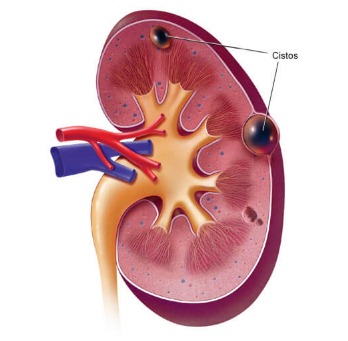

Tenho uma profunda gratidão pelo profissionalismo e humanidade no procedimento de ablação do rim esquerdo realizado pelo Dr. Rafael. Desde a consulta, senti a empatia e preocupação com o meu bem-estar. Dr. Rafael explicou com clareza o procedimento e os possíveis riscos e me tranquilizou com suas palavras. Durante a cirurgia foi extravagante cuidadoso e atencioso e acompanhou de perto minha recuperação. Na alta, que foi no mesmo dia, falou com minha esposa explicando o procedimento. Tem a minha gratidão por sua dedicação e competência. Que Deus abençoe a ele e sua família.

Dr. Rafael é um médico muito humanizado e competente. Meu marido fez uma ablação no rim esquerdo e desde a consulta nos sentimos acolhidos. Quero ressaltar também o atendimento da Laine, secretária, que nos instruiu para que a cirurgia ocorresse dentro do prazo. Obrigada por ser tão atenciosa. Gratidão ao dr. Rafael e sua equipe.